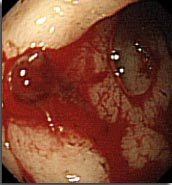

Coloscopie pour diarrhée glaireuse chez un patient ayant eu une antibiothérapie récente, qu’est ce que c’est?

Colite pseudo-membraneuse => clostridium difficile